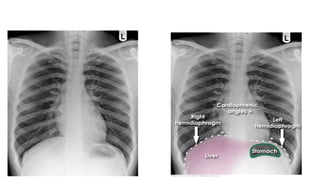

This document discusses key aspects of thorax radiology including positioning for PA and AP views, assessing heart size, visibility of anatomical structures like the scapulae, lungs zones, and measurements like cardiothoracic ratio. It provides guidance on evaluating rotation, inspiration, and penetration on chest x-rays as well as identifying structures like the lobe of azygos vein and aortic knuckle.